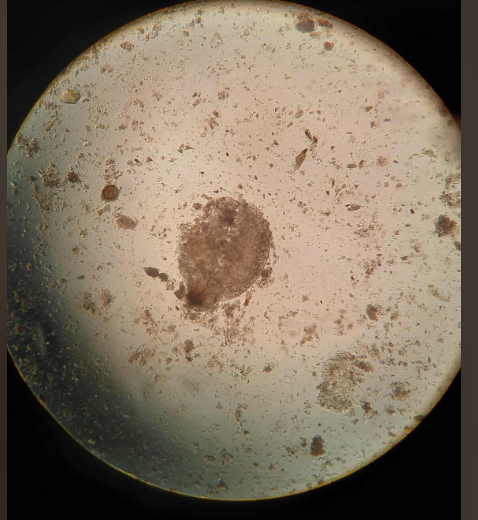

HOOK WORM FILARIFORM W.M

ANCYLOSTOMA CANINUM OVA W.M

DIPYLIDIUM CANINUM OVA

ERYTHOMA PANCREATICUM OVA W.M

FACIOLA HEPATICA

TRICHURIS TRICHIURA OVE WM

HYEMENELOPIS DIMINUTA OVA W.M

TAENIA SAGINATA

ASCARIS LUMBRICOIDES OVE WM

STRONGYLOIDES FILARIFORM WM